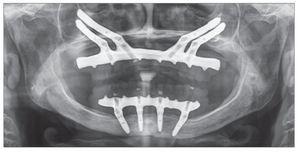

Después de 4 a 6 meses de funcionamiento, los pacientes fueron sometidos a la fase de rehabilitación protésica. La prótesis final se fabricó empleando el sistema Procera CAD_CAM (figs 4 y 5).

Figura 4. Prótesis final fabricada empleando el sistema CAD/CAM de Procera.

Figura 5. Radiografía panorámica de la prótesis final.